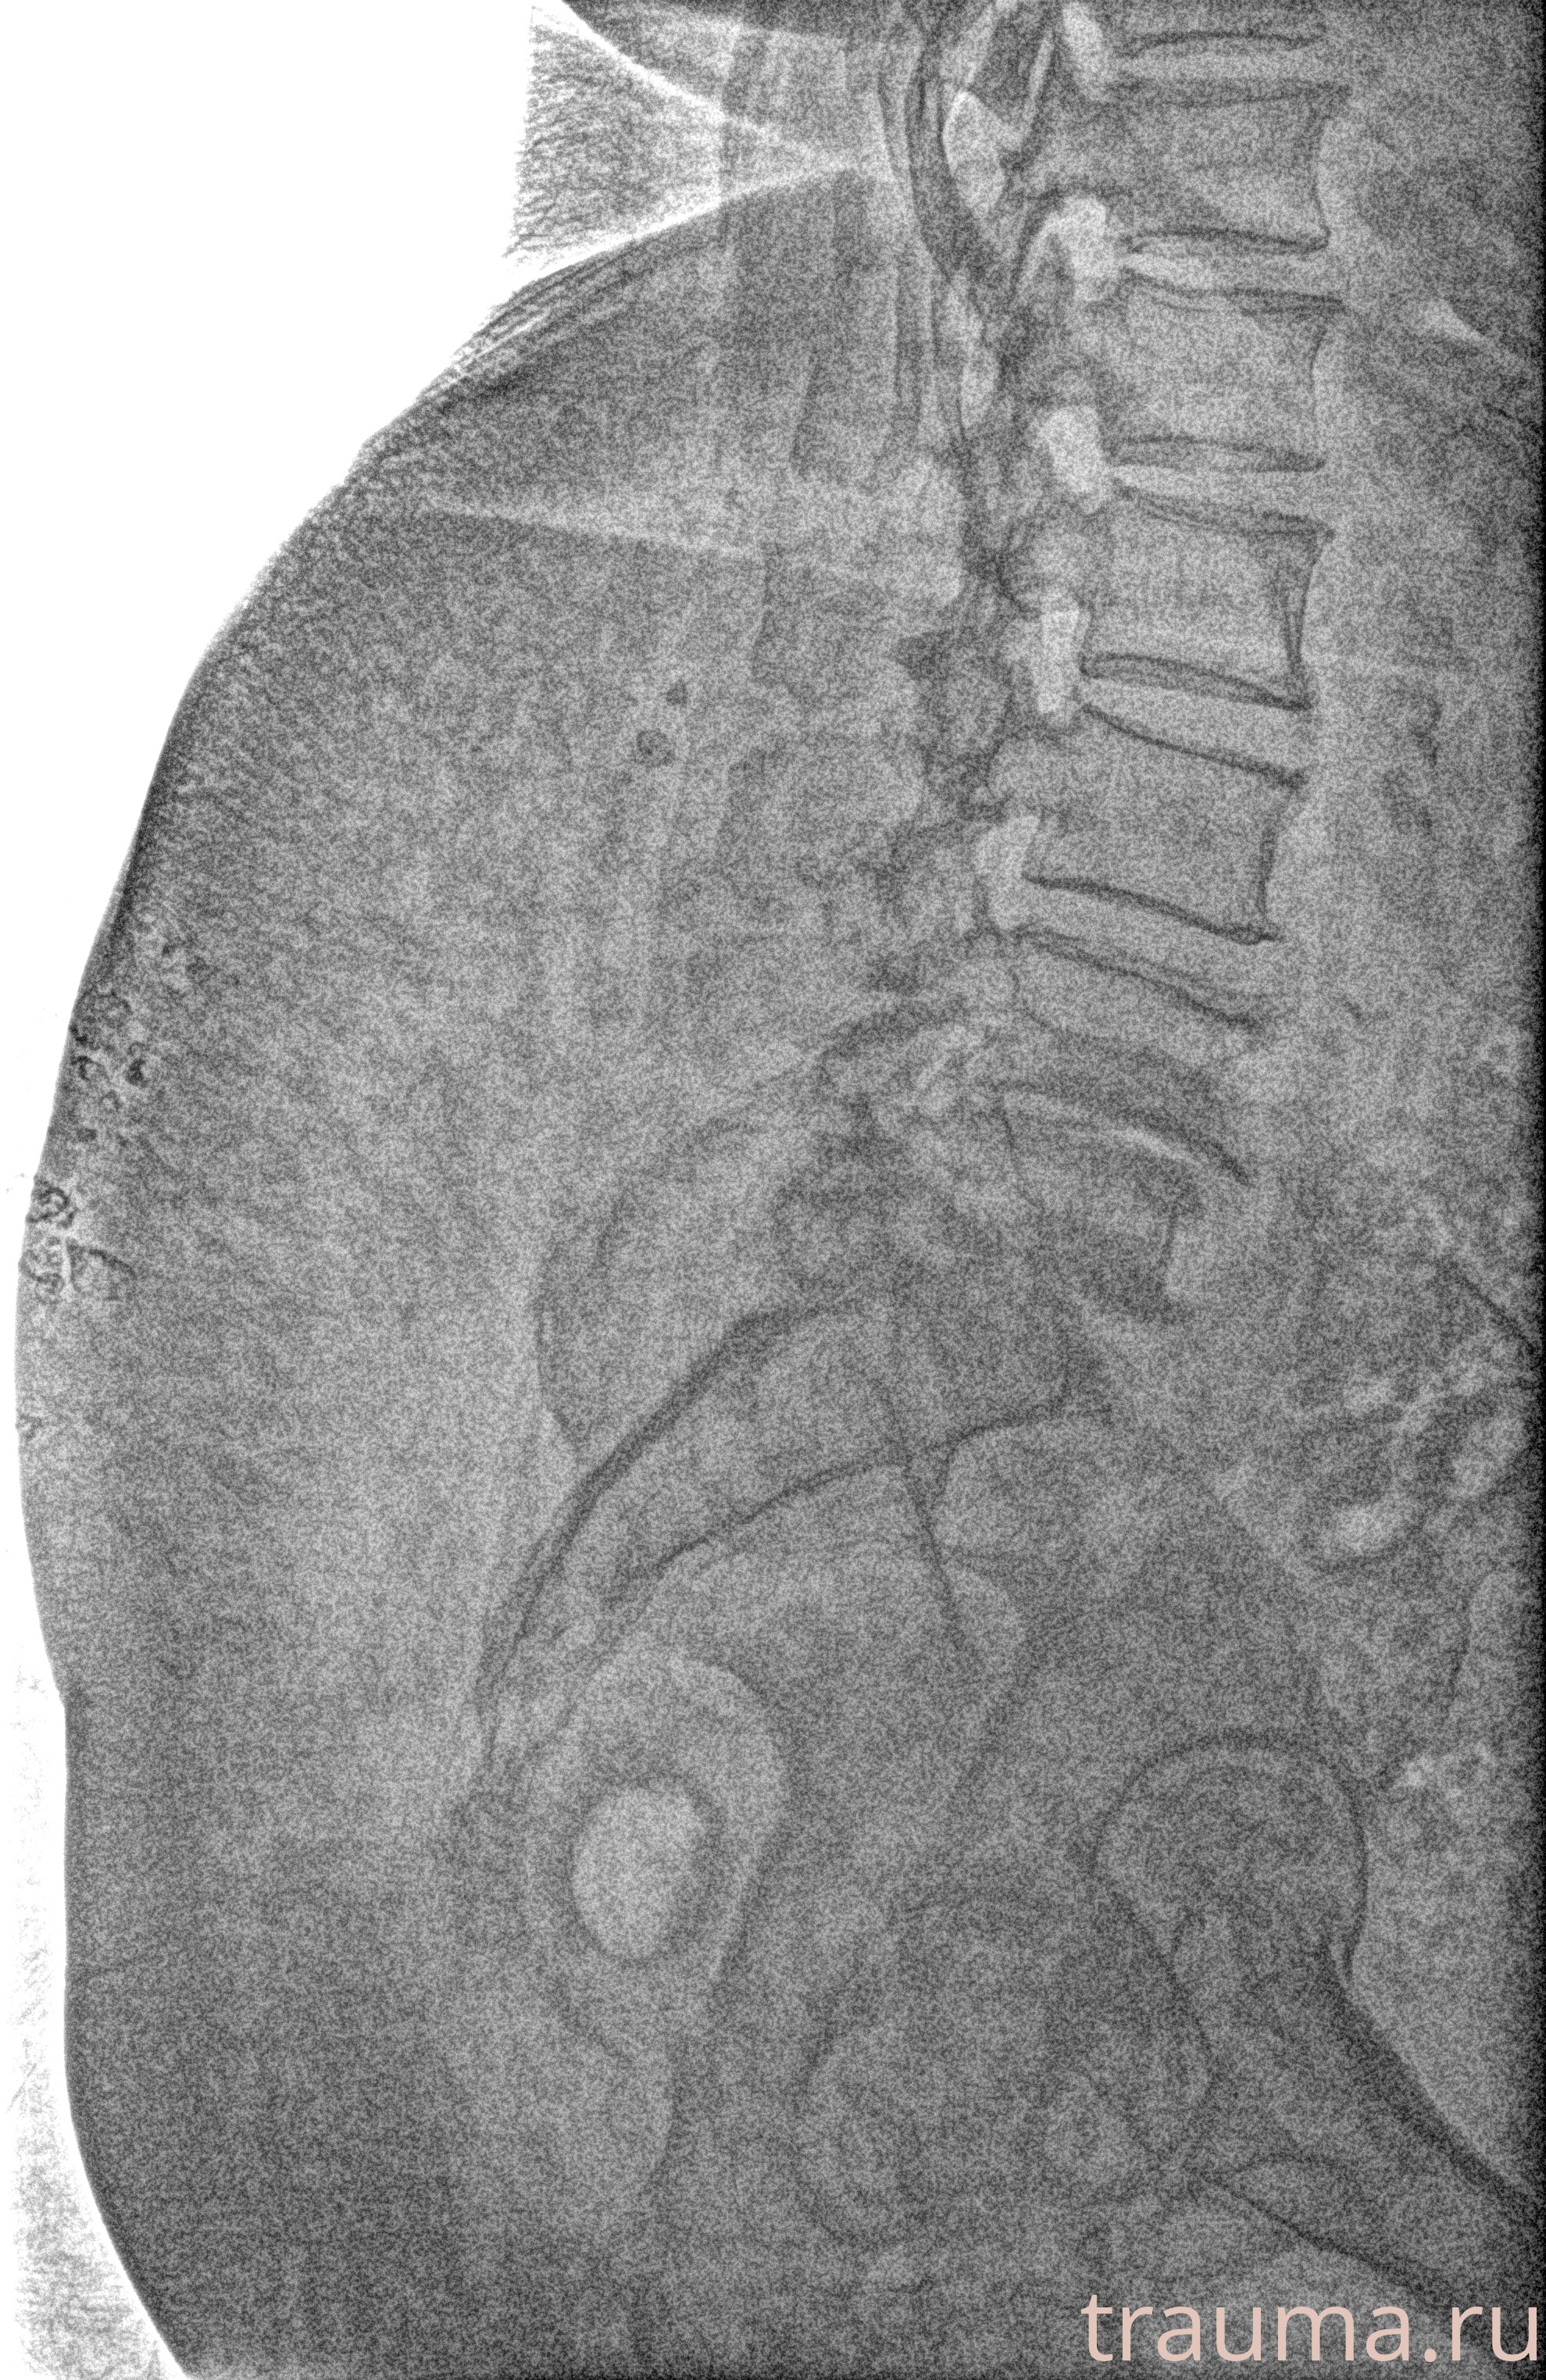

Рентген на дому: по вашему адресу приезжает врач-рентгенолог, травматолог-ортопед с мобильным рентгеновским аппаратом, проводит диагностику травмы или заболевания, делает необходимые рентгенограммы, дает рекомендации по дальнейшему лечению. Получить качественные снимки в домашних условиях возможно благодаря уникальной методике, разработанной МосРентген Центром для института  Склифосовского